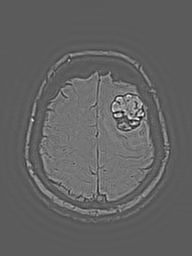

MRI Brain w/ Contrast

Baseline → Follow-up (Δ 14 days)

MRI view

Local Lesion Window · Lesion Origin (Tracked)

Local lesion window

Lesion Origin anchor for longitudinal tracking

ABER anatomic boundary emphasis region

Overlay margin / curvature / global

eigenMRI is a deterministic reconstruction framework that applies eigenmode and Laplacian-based spectral analysis to standard MRI data. It enhances structural continuity, boundary definition, and subtle tissue transitions without modifying scanner hardware, pulse sequences, or contrast agents.